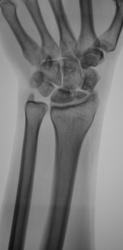

Катенёв Валенти... Дата публикации 13.10.2009, 18:16 Пациент направлен в рентгеновский кабинет хирургом для рентгенографии лучезапястного сустава. Травма. Произведено исследование. pp.1..JPG pp.2..JPG pp.3..JPG pp.4..JPG Ваше мнение коллеги? ВложениеРазмер pp.1..JPG62.4 КБ pp.2..JPG53.6 КБ pp.3..JPG95.92 КБ pp.4..JPG80.54 КБ Втр, 13/10/2009 - 21:14 #1 flagman Не на сайте Был на сайте: 11 лет 5 месяцев назад Зарегистрирован: 05.06.2008 - 20:08 Публикации: 83 странная ладья - неужели перелом? Втр, 13/10/2009 - 21:18 #2 Катенёв Валенти... Не на сайте Был на сайте: 7 лет 3 недели назад Зарегистрирован: 22.03.2008 - 22:15 Публикации: 54876 Один перелом "ладьи"? Втр, 13/10/2009 - 21:29 #3 Павел Владимирович Не на сайте Был на сайте: 16 лет 2 месяцев назад Зарегистрирован: 07.10.2009 - 20:47 Публикации: 11 перелом ладьевидной кости с расхождением отломков Втр, 13/10/2009 - 21:41 #4 Наталия Не на сайте Был на сайте: 8 лет 7 месяцев назад Зарегистрирован: 30.07.2008 - 13:24 Публикации: 538 Двойной перелом ладьевидной кости. Ср, 14/10/2009 - 07:52 #5 v1tal Не на сайте Был на сайте: 4 года 9 месяцев назад Зарегистрирован: 07.06.2008 - 19:41 Публикации: 1779 А как же полулунная ????? Ещё и ладья в предачу. "Знаешь, у некоторых врачей есть комплекс мессии — им необходимо спасать мир. А у тебя комплекс Рубика — тебе необходимо решать головоломки." Ср, 14/10/2009 - 14:38 #6 OPEXOB Не на сайте Был на сайте: 9 лет 11 месяцев назад Зарегистрирован: 26.07.2008 - 10:02 Публикации: 280 Может "снайперы" укажите стрелками, кто, что видет? Ср, 14/10/2009 - 19:48 #7 Глазков Игорь А... Не на сайте Был на сайте: 9 месяцев 2 недели назад Зарегистрирован: 19.12.2008 - 20:41 Публикации: 1597 ладьевидной кости Прийди к Себе

странная ладья - неужели перелом?

Один перелом "ладьи"?

перелом ладьевидной кости с расхождением отломков

Двойной перелом ладьевидной кости.

А как же полулунная ????? Ещё и ладья в предачу.